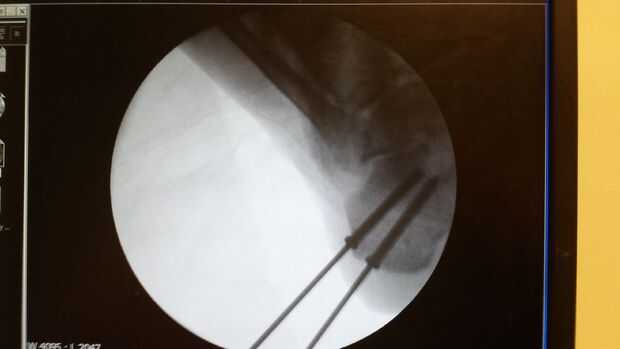

Paso 1: Aquí está mi talón, y aquí están algunas partes

Aquí está mi talón. EW.